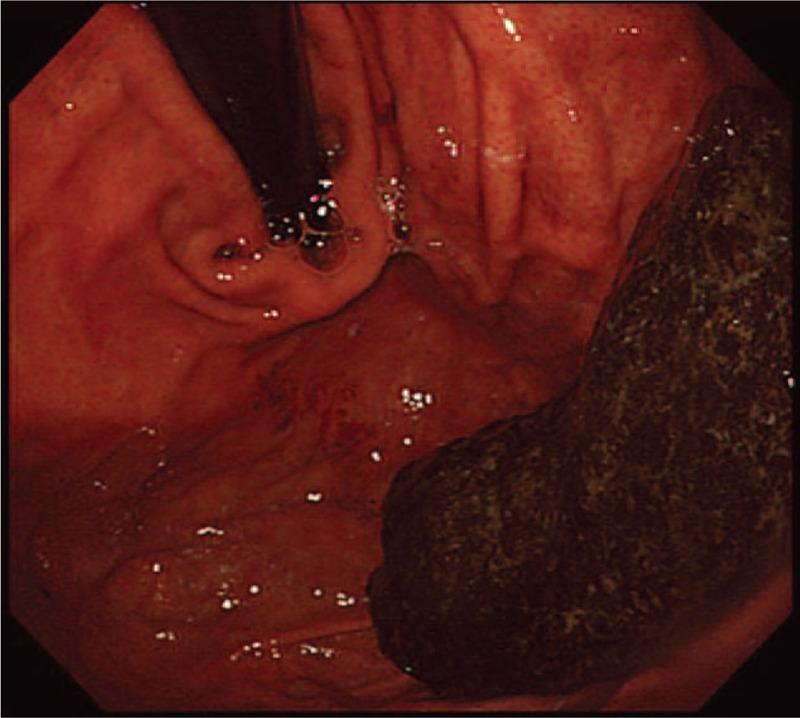

An upper gastrointestinal (GI) endoscopy performed which revealed an 8 × 5-cm intragastric diospyrobezoar with an adjacent necrotic pressure ulcer of size 0.8 × 0.5-cm without signs of bleeding.

进行了上消化道内镜检查,发现一个8×5厘米的胃内柿石,相邻有一个大小为0.8×0.5厘米的坏死性压疮,无出血迹象。